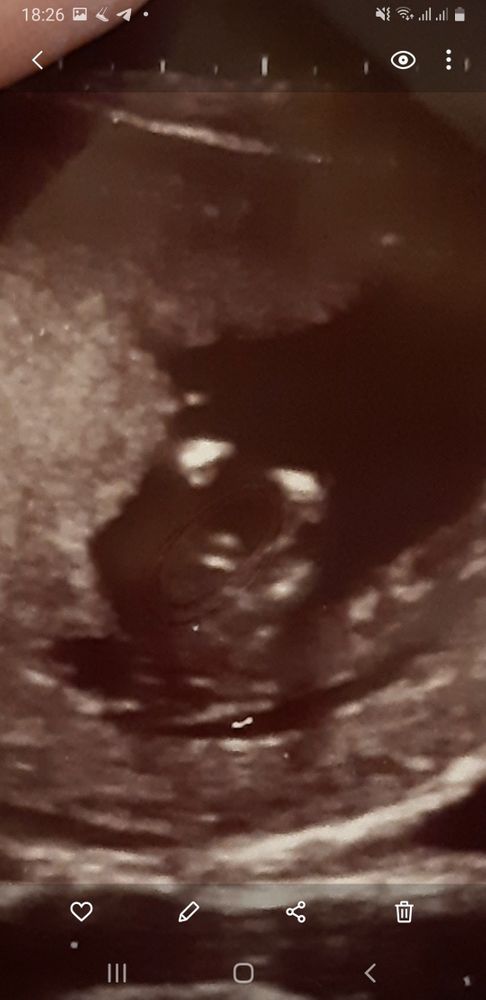

Вот фото с узи, может кто понимает, как они определяют)))) Точно скорее всего мальчик?

Мне тоже 12 недель сказали , мальчик 100%. Врач сама предложила пол сказать ,говорит мальчик

- мальчик без сомнений

Мальчик 99 и 9 судя по УЗИ вашему . Очень задран половой бугорок . У девочек так не бывает . Мне оба раза в 10 недель правильно про сказали . В этот раз ещё и нипт подтвердил потом